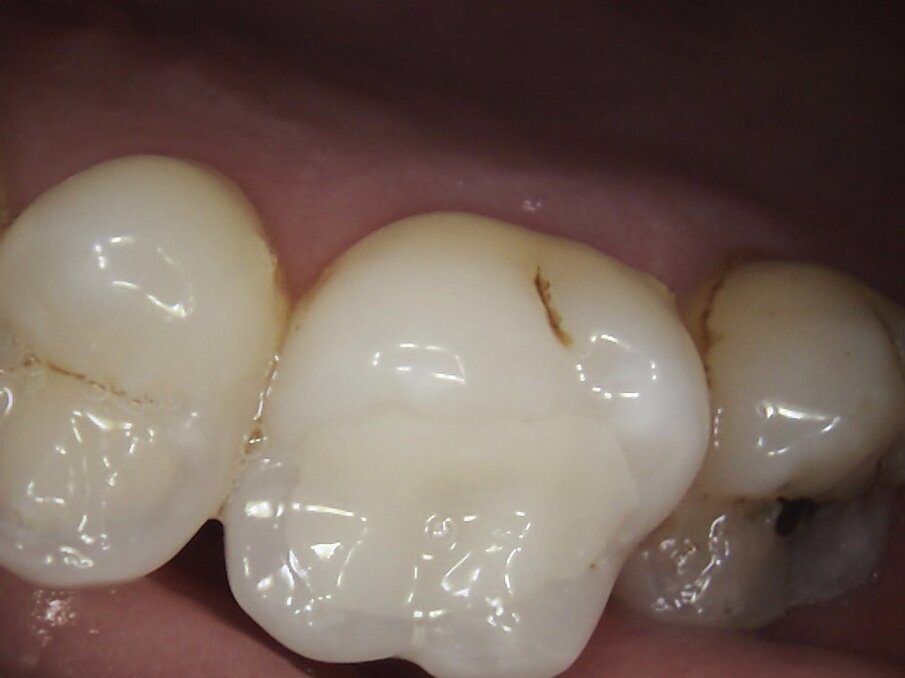

On examination, teeth 16 and 46 had amalgam restorations, with defective margins and signs of corrosion of the metal into the surrounding dentinal tubules. Tooth 46 had a vertical fracture running from occlusal surface to 1mm coronal if the gingiva on the palatal aspect. Neither tooth was tender to percussion and both scored positively with electric pulp testing. However, 46 did have pain on release when biting on the palatal cusps of the crack finder. The patient confirmed this was the sensation she had been experiencing over the last few months. Two periapical radiographs confirmed caries under each amalgam restoration but no evidence of periapical pathology.

I suggested removing each amalgam restoration and any stained dentine and fractures and restoring the teeth with Inlays fabricated by CAD/CAM system, MyCrown.